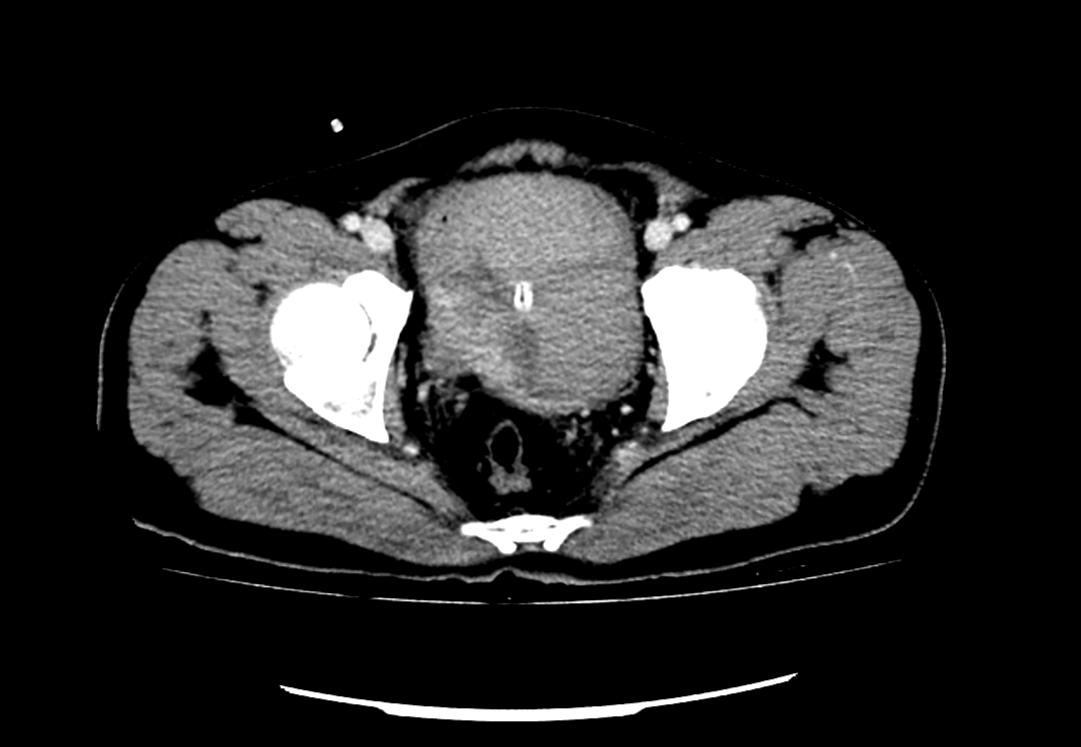

患者為53歲的男性,患者因肉眼血尿就診我院門(mén)診,行泌尿系CT考慮膀胱占位,建議患者住院治療,入院后完善膀胱MRI檢查進(jìn)一步診斷膀胱腫瘤,侵犯肌層。行膀胱腫物激光切除后,病理學(xué)檢查明確“膀胱高級(jí)別尿路上皮癌,肌層浸潤(rùn)”診斷,結(jié)合泌尿外科診療指南建議行根治性膀胱全切術(shù)。

泌尿外科醫(yī)生團(tuán)隊(duì)術(shù)前將患者情況上報(bào)醫(yī)務(wù)科,并組織了多次會(huì)診?;颊?/span>“肌層浸潤(rùn)性膀胱癌”診斷明確,術(shù)前完善心肺功能排除無(wú)明顯手術(shù)禁忌,結(jié)合指南推薦及泌尿外科團(tuán)隊(duì)成員綜合意見(jiàn),決定在全麻下行腹腔鏡下膀胱根治性切除+盆腔淋巴節(jié)清掃+回腸代膀胱手術(shù)。術(shù)前嚴(yán)格完善準(zhǔn)備工作,手術(shù)歷經(jīng)7小時(shí),完整切除了患者的膀胱、前列腺及精囊,并行回腸代膀胱。手術(shù)順利,術(shù)后3天可正常行走,復(fù)查患者各項(xiàng)指標(biāo)正常。